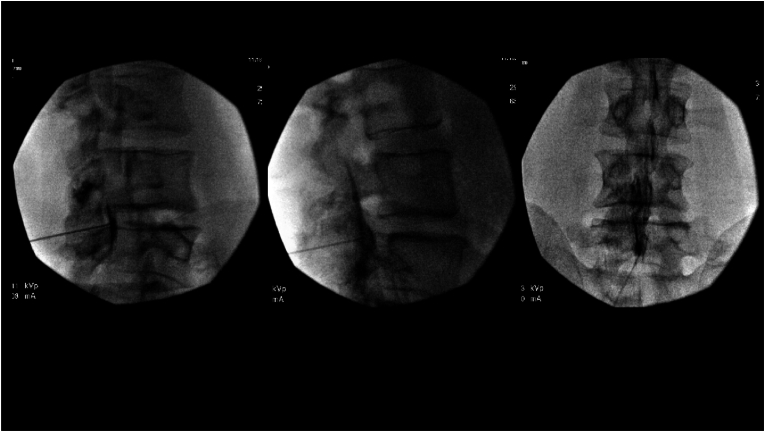

AP (A) and lateral (B) fluoroscopic views during interlaminar epidural steroid injection showing contrast localized to the epidural space.

7. Fluoroscopic confirmation: Lateral view to confirm needle depth — the tip should be at or just past the ligamentum flavum

8. Contrast injection: 1-2 mL of non-ionic contrast under real-time fluoroscopy to confirm epidural spread pattern in at least two planes (AP plus CLO or lateral)

Contralateral Oblique (CLO) View — per IPSIS

The IPSIS Technical Manual identifies the CLO view as superior to the lateral view for interlaminar epidural access:

• The CLO view is obtained by positioning the X-ray detector contralateral to the needle tip, projecting the X-ray beam parallel to the target-side lamina

• Optimal CLO angle is approximately 45-60 degrees from AP, varying by spinal segment

• The ventral interlaminar line (VILL) connects the anterior margins of consecutive laminae and represents the earliest expected location of loss of resistance

• CLO provides better needle tip visualization, more consistent epidural space identification, and ability to redirect after a false LOR compared to lateral view